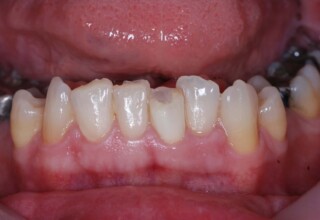

Οι όψεις ρητίνης προσφέρουν έναν οικονομικό τρόπο αισθητικής βελτίωσης της εμφάνισης των προσθίων δοντιών ενίοτε και των προγομφίων. Οι δυνατότητες τους πολλές, μπορούν να κάνουν και θαύματα! Ο μονός περιορισμός η κλινική ευχέρεια και η φαντασία του επεμβαίνοντος. Σε αυτήν την ασθενή οι τέσσερεις άνω τομείς είχαν ο καθένας το δικό του πρόβλημα(δυσχρωμία, απόκλιση) και επιπλέον: διαστήματα, πολλαπλές αποχρώσεις, κακή σχέση μεταξύ τους και με τα ούλα. Αποκαταστάθηκαν με τέσσερεις άμεσες όψεις ρητίνης (η μια πάνω σε στεφάνη πορσελάνης εμφυτεύματος!!!) οι οποίες κατασκευάστηκαν ενδοστοματικά!